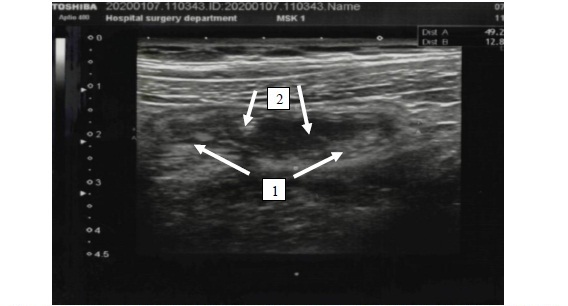

The results of the study. The ultrasound signs of acute appendicitis included the presence of a blindly ending tubular structure at the point of maximum pain with an outer diameter of more than 6 mm, which cannot be compressed, aperistalsis, wall thickness more than 2 mm, and the presence of coprolite in the lumen of the tubular structure (fig. 1). In transverse scanning, the tubular structure was in the form of a «target», «cockade»; the thickness of the stromal component of the wall of the appendix was more than 1.5 mm (fig. 2).

Fig. 2. An echogram of the vermiform appendix: 1 – portions of the tubular formation with thickened walls, with a «double contour» («convoluted vermiform appendix») are visualized; 2 – the top of the appendix, ending blindly